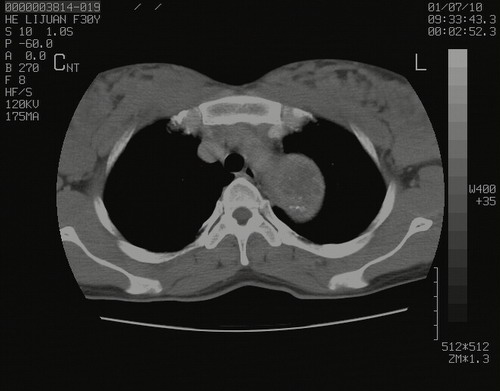

怀孕3个月时(2009-3至4月间),自述突感左侧前后胸疼痛1天,以前胸明显,随后偶感闷痛,余未见异

左肺尖脊柱旁沟肿块,境界清楚,边缘光滑,密度不均,内有多发点片状钙化,考虑良性肿瘤,骨软骨瘤或神经源性肿瘤可能,肺错构瘤不除外。

左后上纵隔见一类圆形肿块影,外侧边界清,密度不均匀,内可见点状钙化影,增强呈不均匀强化,考虑神经源性肿瘤可能。期待病理结果。